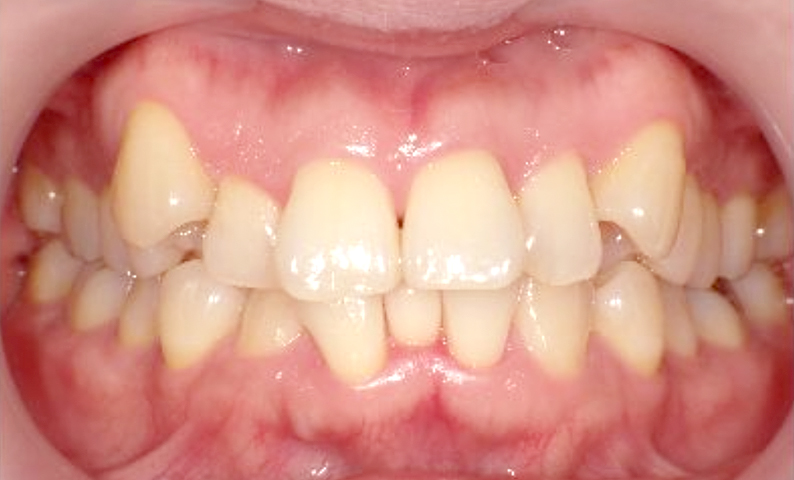

症例_002 上顎だけの部分矯正

治療期間:7ヶ月金額:30万円+税女性前歯のガタガタ上の前歯だけ

| Before | After |

|---|---|

|